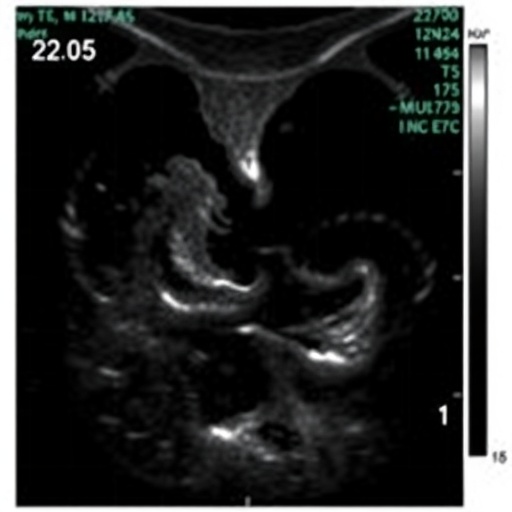

It's early morning and a team of more than 20 professionals cram around a long table in a dark room, peering at slide after slide of black-and-white mammogram images crossing the screen.